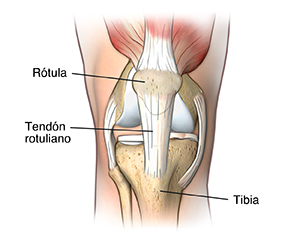

La rodilla de basquetbolista, también conocida como tendinitis rotuliana, es una afección que se caracteriza por la inflamación del tendón rotuliano. Este tendón conecta la rótula (patela) con el hueso de la espinilla (tibia). La rodilla de basquetbolista debilita el tendón y, si no se la trata, puede llevar a desgarros en el tendón.

La rodilla de basquetbolista es la inflamación del tendón rotuliano, el tendón que conecta la rótula (patela) con el hueso de la espinilla (tibia).